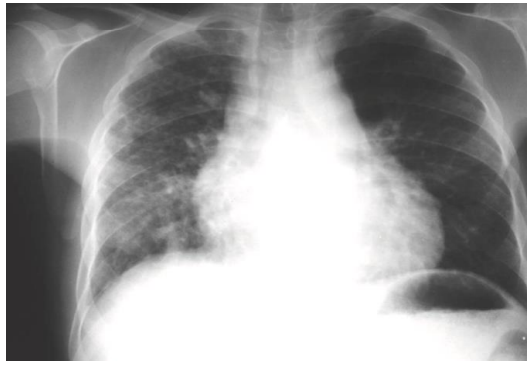

Jonas, 17 anos, portador de drepanocitose, comparece ao pronto atendimento com

relato de dor torácica, taquipneia, febre, tosse e dispneia. Ao exame clínico, ausculta pulmonar sem ruídos adventícios. FR 26 irpm, oximetria 92% em ar ambiente.

Laboratório evidenciou leucocitose. Radiografia de tórax segue abaixo:

Sobre o quadro em questão, é INCORRETO afirmar: